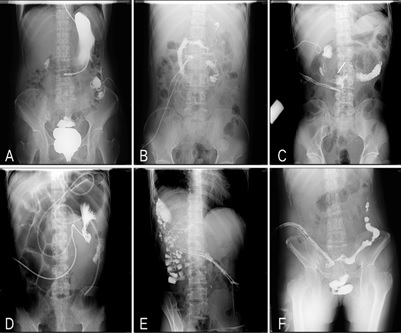

• Diagnosed with intestinal fistula through imaging studies: Patients must have a confirmed diagnosis of intestinal fistula based on imaging studies (Figure 1).

Figure 1: Imaging pictures of several cases of typical intestinal fistulas. A: Fistulae in the stomach and splenic flexure of the colon. B: Fistula in descending part of duodenum.C: Fistula in horizontal part of duodenum. D: Fistula in the jejunum.E: Fistula in the hepatic flexure of the colon.F: Fistula in the sigmoid colon.